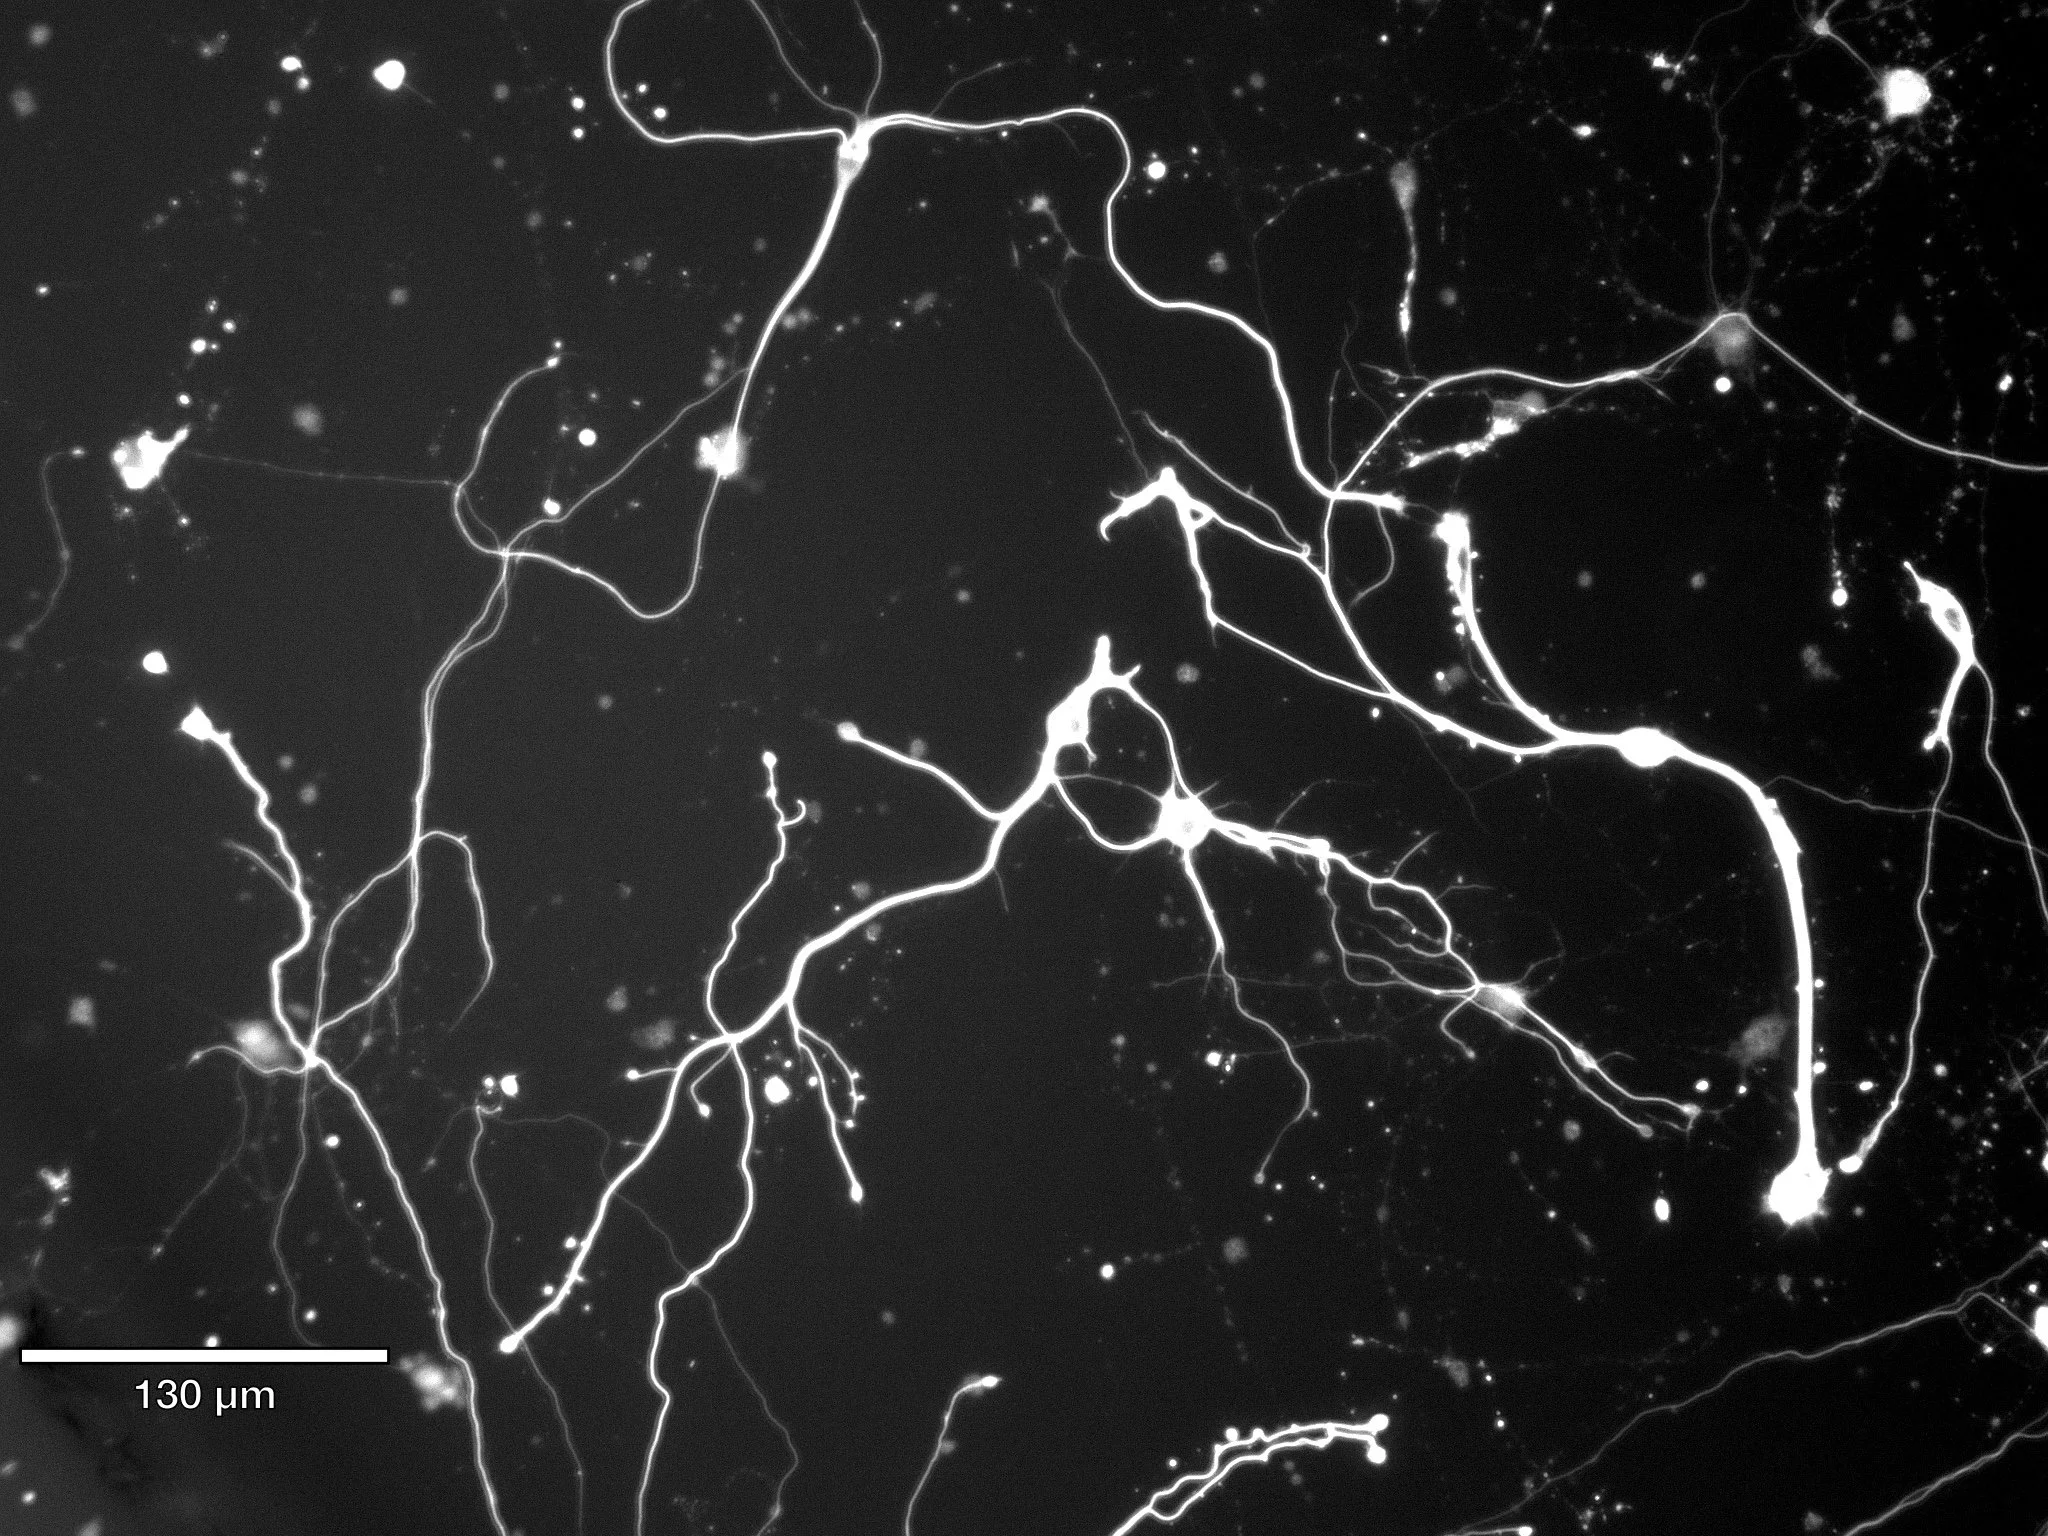

Novel High-order Algorithm on 3D Spline for Modeling Biological Neuron Growth

Custom C++ high performance algorithm for solving high-order nonlinear biophysics process on high-fidelity locally refined THB-splines

K. Qian, Y. J. Zhang. 3D neuron growth model using truncated hierarchical B-splines with multi-level local refinements.Computer Methods in Applied Mechanics and Engineering, 442, 118003, 2025.

ML Future Frame Prediction (Video) using MetaFormer Attention for Biological Cultures

Future video prediction architecture for biological neurite outgrowth and deterioration.

K. Qian, G. O. Suarez, T. Nambara, T. Kanekiyo, Y. J. Zhang. High-throughput machine learning framework for predicting neurite deterioration using MetaFormer attention.Computer Methods in Applied Mechanics and Engineering 442, 118003, 2025.

Computational Modeling of Alzheimer's disease with Real Patients’ Neuron Cell

K. Qian, G. O. Suarez, T. Nambara, T. Kanekiyo, A. S. Liao, V. A. Webster-Wood, Y. J. Zhang. Neurodevelopmental Disorders Modeling using Isogeometric Analysis, Dynamic Domain Expansion and Local Refinement. Computer Methods in Applied Mechanics and Engineering, 433: 117534, 2025.